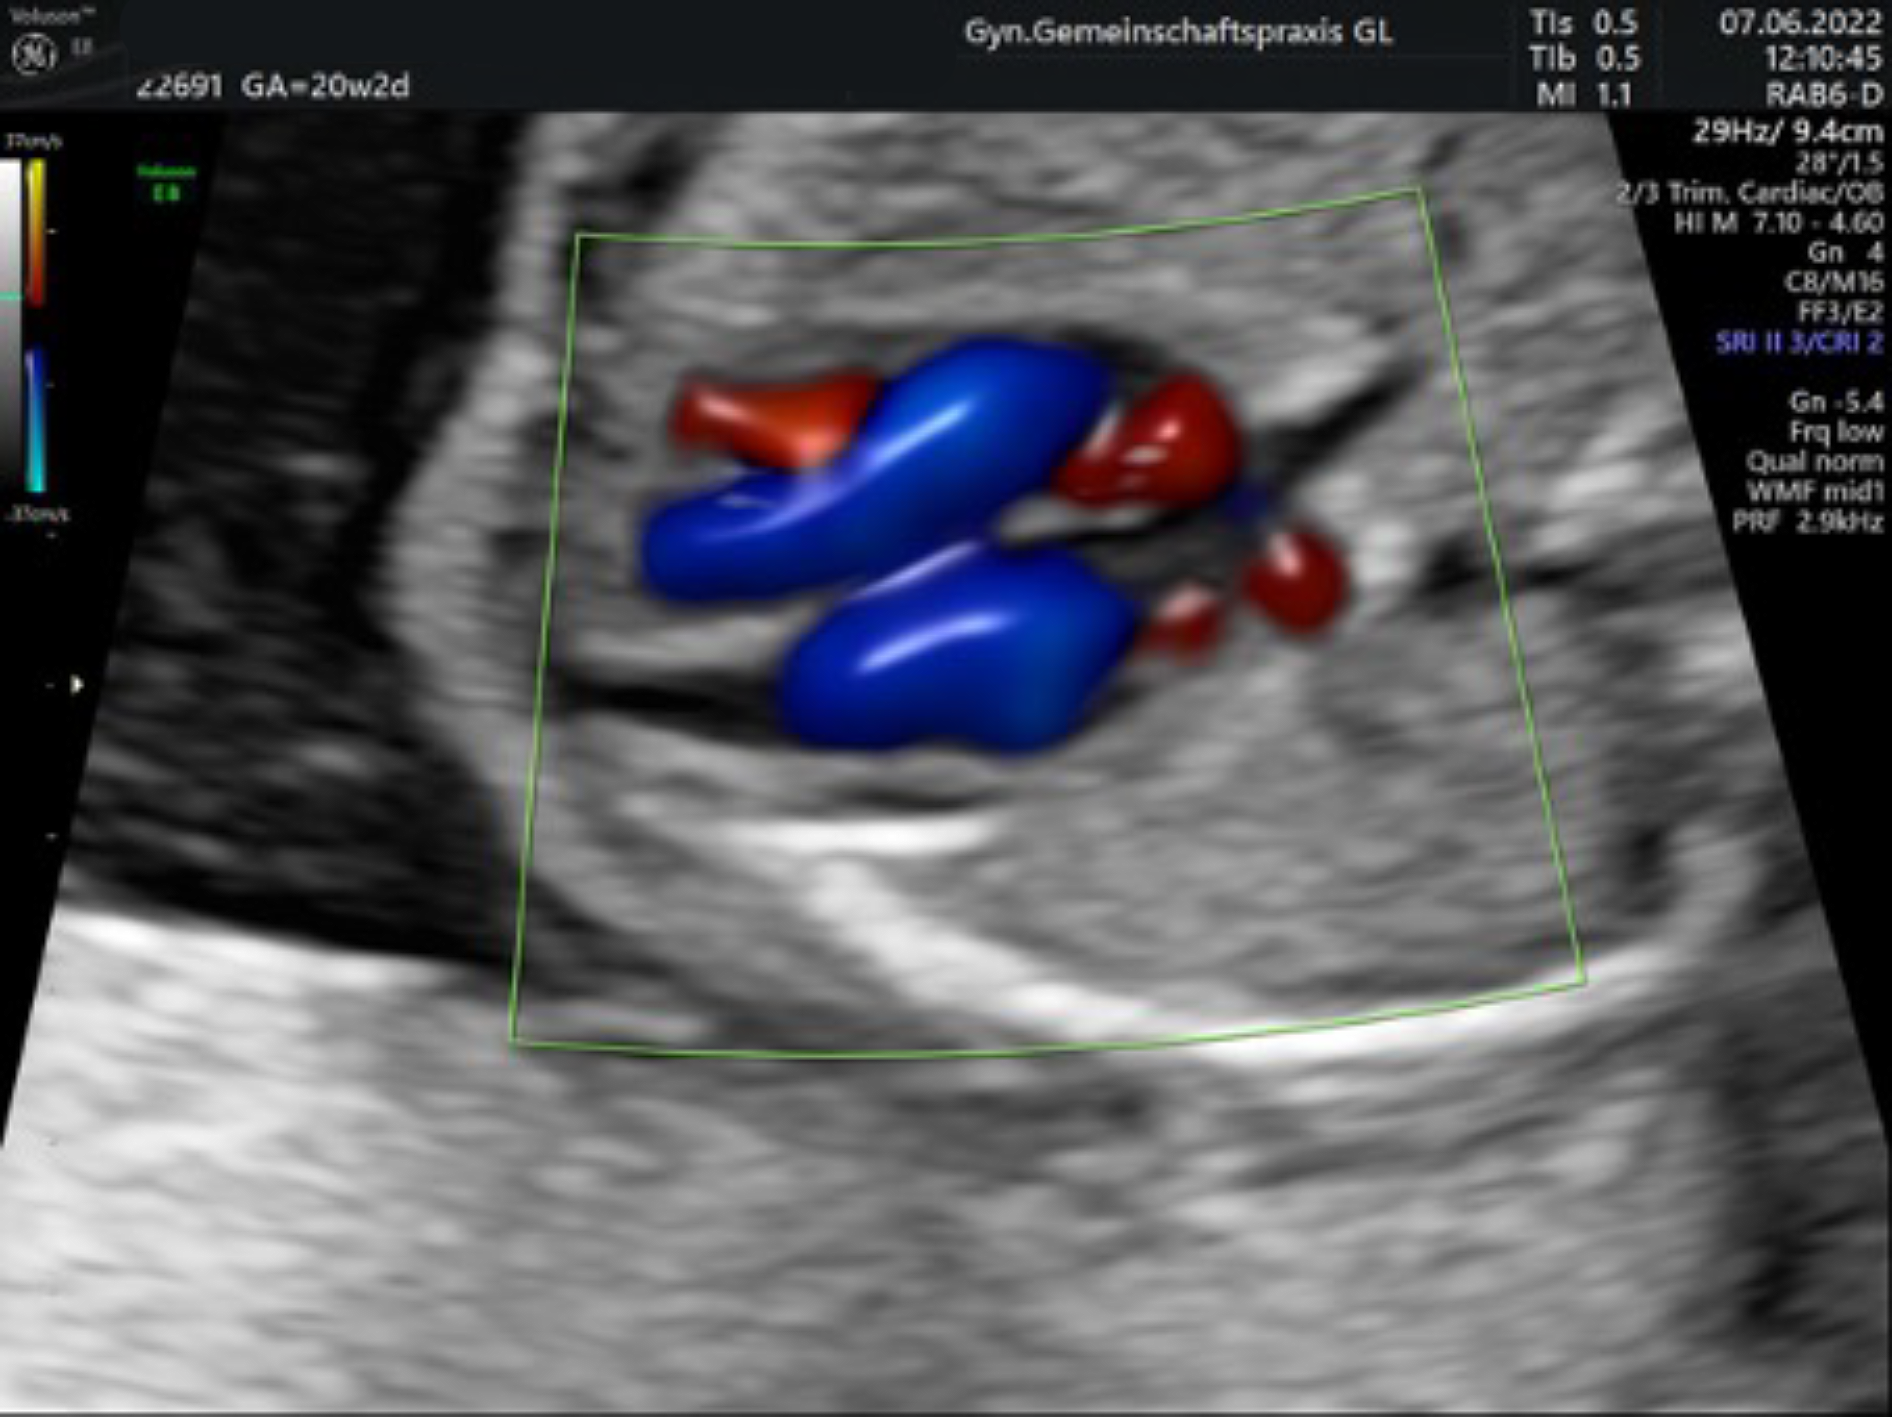

Ultraschall in der 20. – 22. Schwangerschaftswoche mit Organfehlbildungsdiagnostik und Untersuchung der Blutversorgung nach den Richtlinien der DEGUM Stufe II

Mit einem hochauflösenden Ultraschallgerät werden dabei alle Organsysteme des Kindes gründlich untersucht um nach Hinweisen auf Fehlentwicklungen zu suchen. Besonderes Augenmerk liegt dabei auf dem Herzen, dessen richtiger Aufbau und Funktion mithilfe farbcodierter Blutflussmessungen (Doppleruntersuchung) überprüft wird.

Auch die Versorgung des Kindes durch die Mutter kann gemessen werden. Hierbei können sich auch frühe Hinweise auf eine spätere sogenannte „Schwangerschaftsvergiftung“ der Mutter finden.